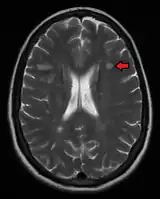

Multiple sclerosis as seen on MRI

Clinical data alone may be sufficient for a diagnosis of MS if an individual has had separate episodes of neurological symptoms characteristic of the disease.[54] In those who seek medical attention after only one attack, other testing is needed for the diagnosis. The most commonly used diagnostic tools are neuroimaging, analysis of cerebrospinal fluid and evoked potentials. Magnetic resonance imaging of the brain and spine may show areas of demyelination (lesions or plaques). Gadolinium can be administered intravenously as a contrast agent to highlight active plaques and, by elimination, demonstrate the existence of historical lesions not associated with symptoms at the moment of the evaluation.[54][55] Testing of cerebrospinal fluid obtained from a lumbar puncture can provide evidence of chronic inflammation in the central nervous system. The cerebrospinal fluid is tested for oligoclonal bands of IgG on electrophoresis, which are inflammation markers found in 75–85% of people with MS.[54][56] The nervous system in MS may respond less actively to stimulation of the optic nerve and sensory nerves due to demyelination of such pathways. These brain responses can be examined using visual- and sensory-evoked potentials.[57]